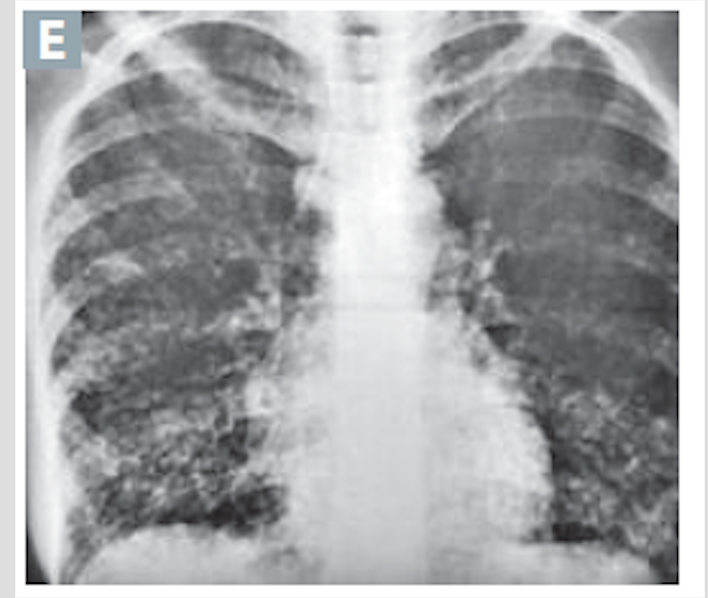

Acute inflammatory infiltrates from bronchioles into adjacent alveoli; patchy distribution involving more that one lobe

Bronchopneumonia